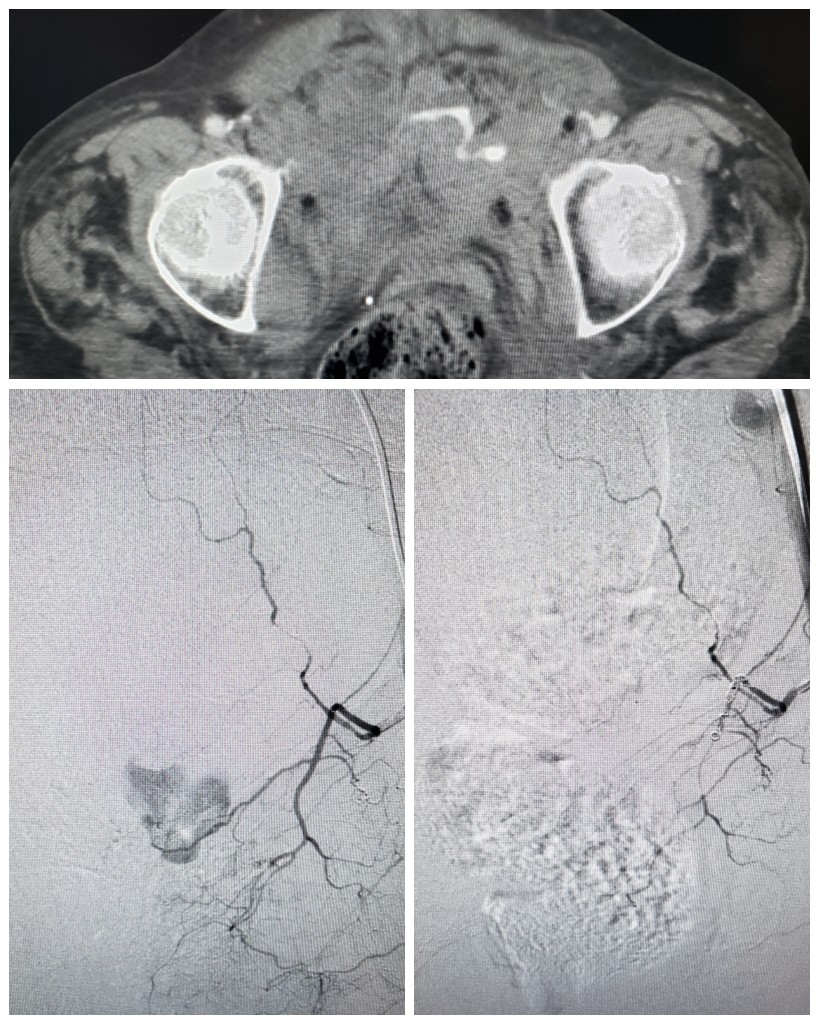

Very satisfying to remove these when appropriate in conjunction with other minimally invasive approaches #venaseal #Ablation #sclerotherapy